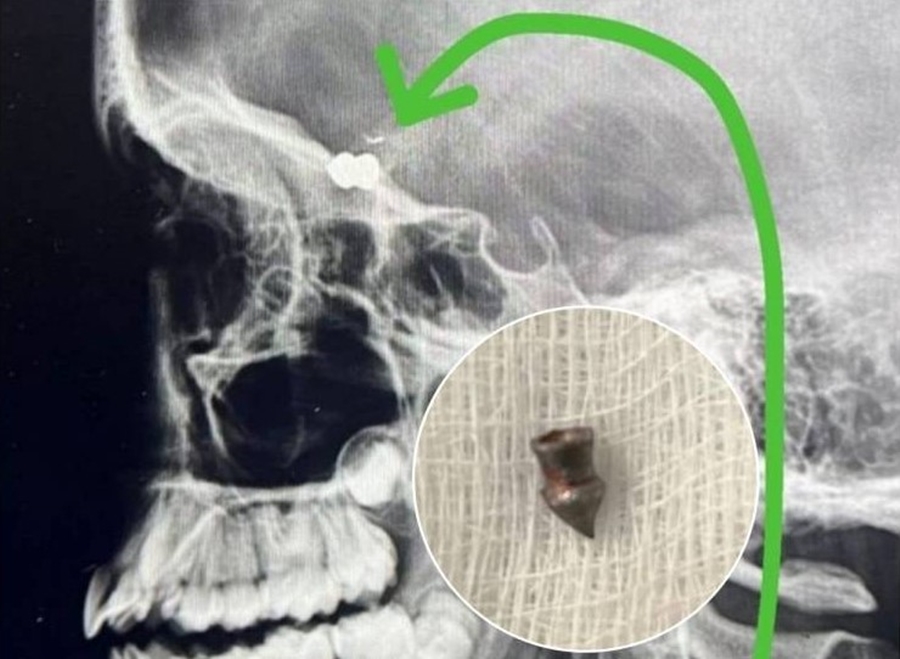

De início, os parentes imaginaram se tratar de ferimento provocado por algum inseto